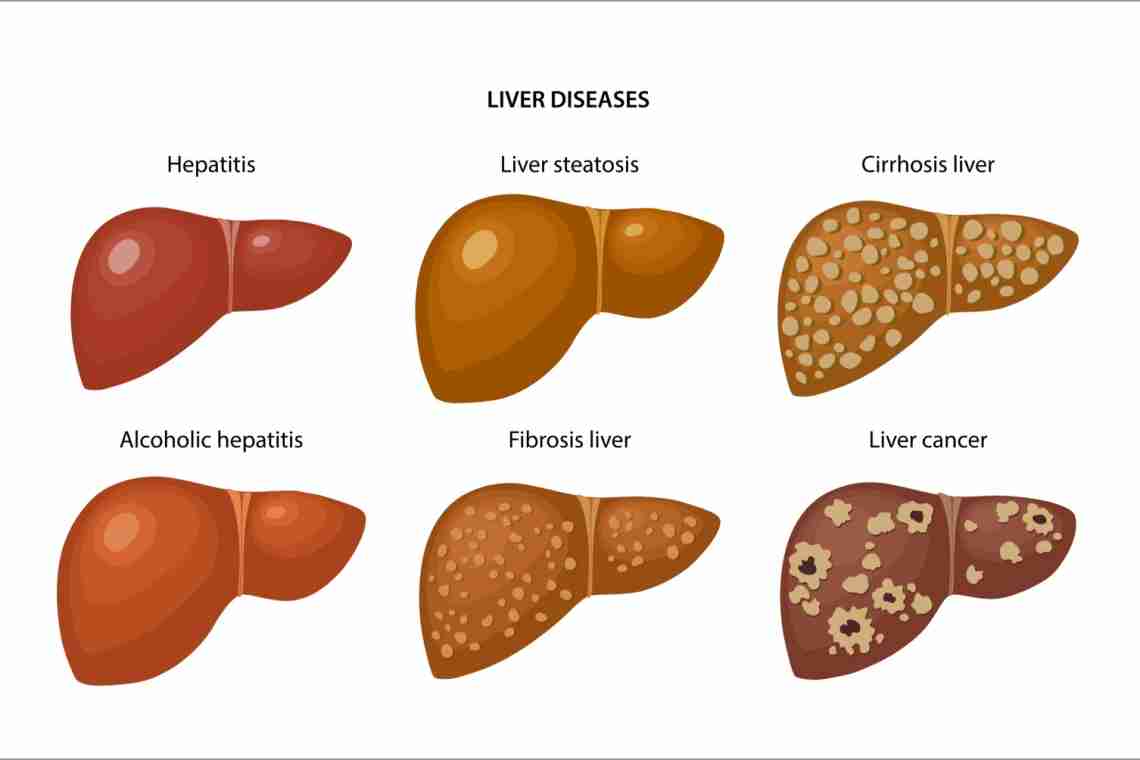

Изображения заболеваний печени: признаки и симптомы